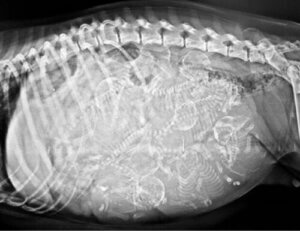

Yavru köpeğin görünümü bundan daha atipik olamazdı. Beyaz kürklü küçük bu köpeğin alnında kocaman bir gözü ve ağzının her iki tarafından çıkıntı yapan 2 büyük dili vardı. Gözü baş yapısında çok fazla yer kapladığı için burnu yoktu.

Oldukça şaşırtıcı olsa da, bu köpeğin hikayesi hayvanlar aleminde tek değil. Siklopia, birçok hayvanda meydana gelen, 2 gözün füzyonu ve alobar holoprozensefali – serebral hemisferlerin gelişememesinden kaynaklanan merkezi bir gözün varlığıyla karakterize edilen ana bir konjenital malformasyondur.